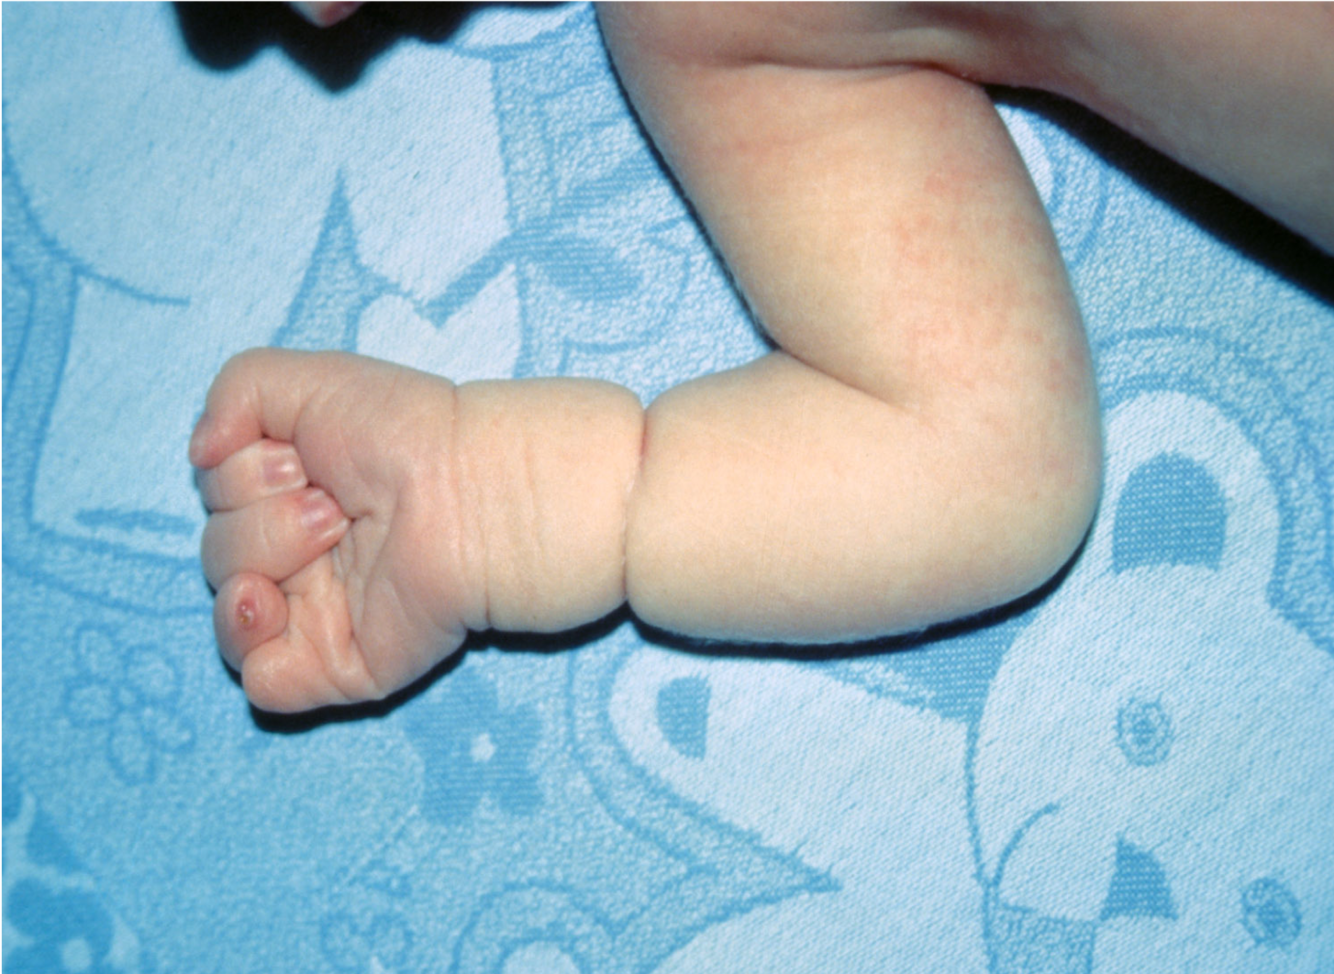

Finger descriptions:

what do these terms mean?

when can Malformationoccur and what is an example?

Malformation: Polysyndactyly - what is it?

extra finger/toe with fusing

Polydactyly is the presence of extra fingers or toes, and syndactyly is the fusing together or webbing of two or more fingers or toes

Deformation in terms of these fingers

Disruption in terms of finger not being present